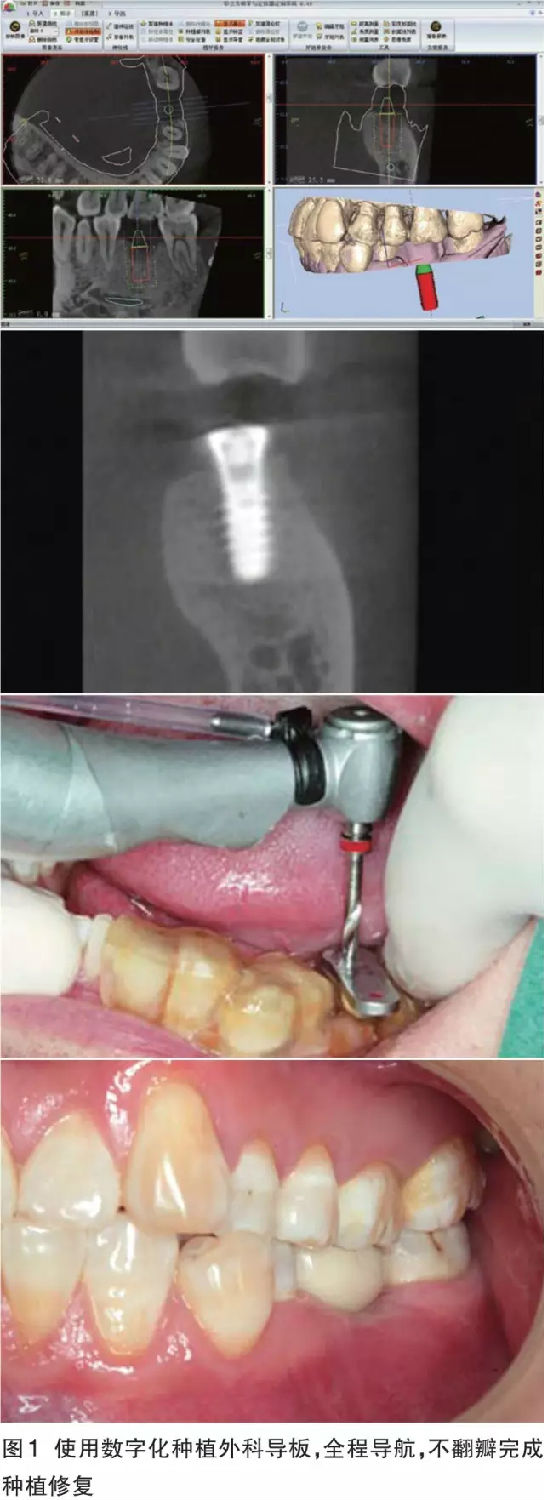

數(shù)字化導(dǎo)板的優(yōu)勢 對于軟硬組織充足、解剖條件好,導(dǎo)板能夠容易精準(zhǔn)就位的病例,如果患者經(jīng)濟(jì)條件允許,全套的數(shù)字化解決方案可以預(yù)見性地、完美地、即刻恢復(fù)缺失牙患者的美觀和功能。同時(shí)可以幫助無經(jīng)驗(yàn)的醫(yī)師規(guī)避重要解剖結(jié)構(gòu)、減少外科風(fēng)險(xiǎn)、獲得術(shù)前根據(jù)修復(fù)效果設(shè)計(jì)的最佳種植體位置(圖1)。